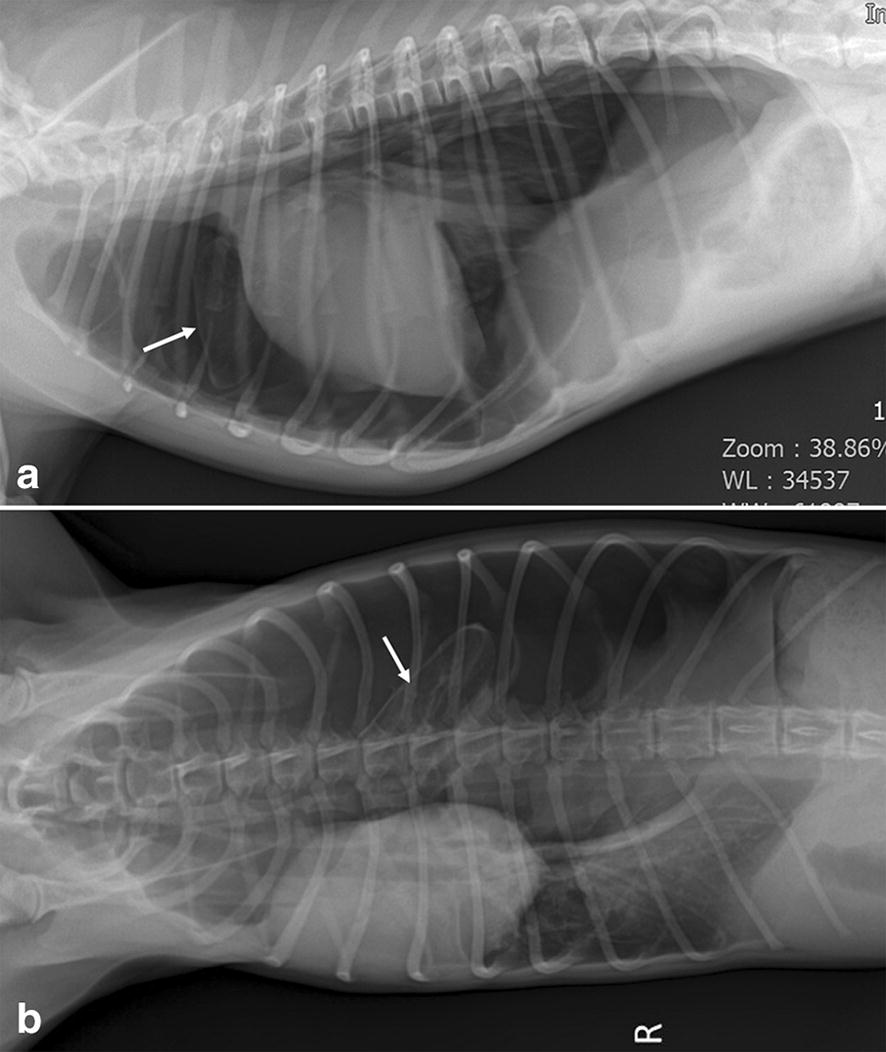

Fig. 1.

Right lateral (a) and dorsoventral (b) thoracic radiographs before emergent thoracocentesis. Large volume of air is retained in the left pleural cavity representing loss of sternal contact of the heart, gas in the left hemithorax, right mediastinal shift, and caudal displacement of the diaphragm with diaphragmatic tenting. The left cranial and caudal lung lobes are collapsed, while the left cranial lung lobe is hyperlucent with scant vascular markings (white arrows) compared to the other collapsed lung lobes